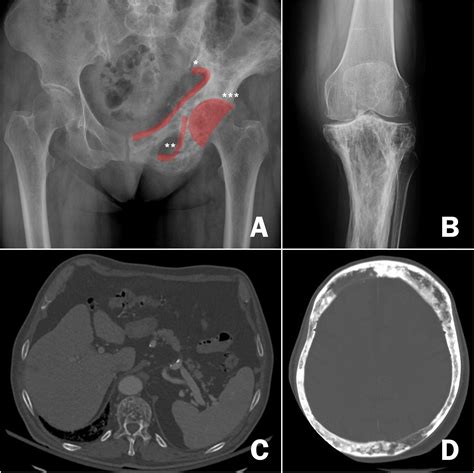

• Imaging tests: X-rays, CT scans, MRI, and bone scans can help visualize the affected bones and assess the extent of the disease.